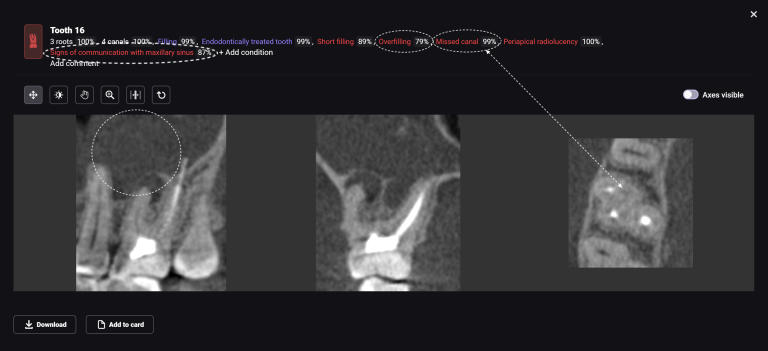

Diagnocat determined not only the presence, but also the localization of the focus of radiolucency of enamel and dentin, which was correctly indicated as “signs of caries” in the report

During a clinical examination, it is difficult to verify the presence of caries located under a filling, which is why the information obtained during a radiological examination is so important

Please note that despite the fact that the radiolucent area is poorly visible when viewing CBCT, Diagnocat reflected in the report the presence of signs of caries and accurately indicated the localization

The presence of a structured report allows the clinician to set up the patient for timely treatment and build a consistent plan for therapeutic dental treatment